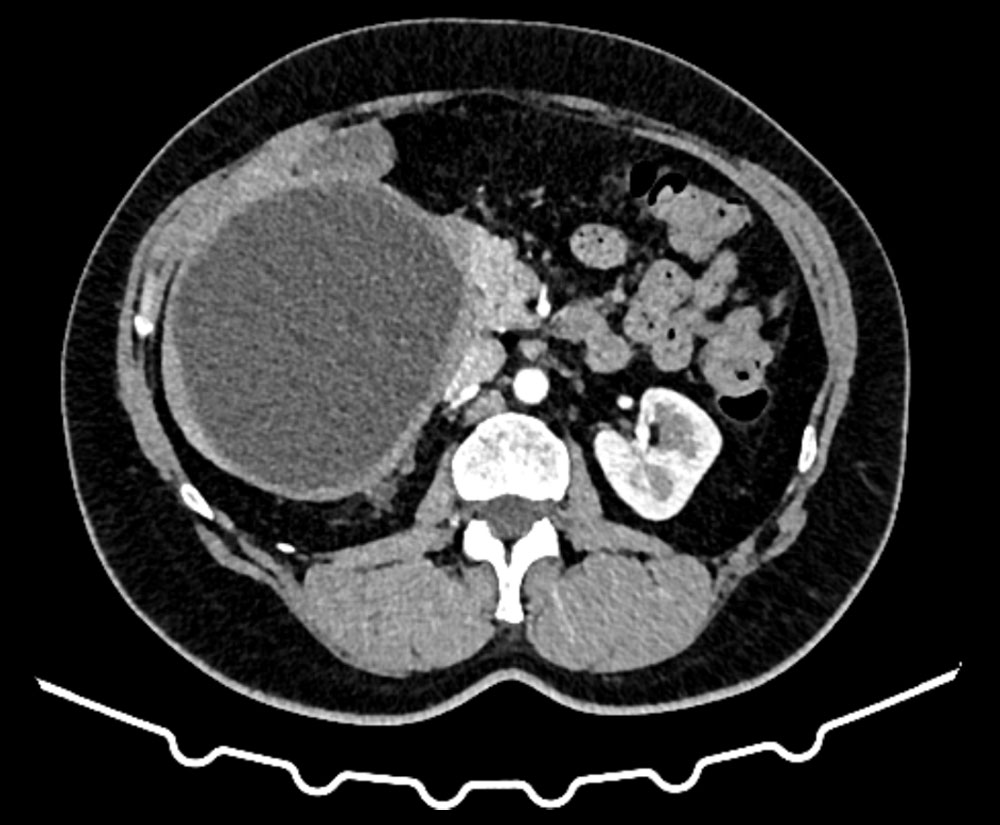

Непаразитарные кисты могут быть врождённой особенностью (истинная киста) или являться последствием перенесенной ранее травмы (псевдокиста) (рис. 2). Кисты печени могут быть следствием перенесённых ранее операций, содержимым таких кист может быть желчь.

Рис. 2. КТ псевдокисты селезёнки

С целью диагностики и определения тактики лечения используются лабораторные и инструментальные методы: стандартные анализы дополняются серологическими тестами на выявление паразитарной активности и опухолевыми маркёрами (СА19,9; РЭА); ультразвуковая диагностика, компьютерная томография с внутривенным контрастированием, магнитно-резонансная томография. В Пироговском Центре возможно прохождение всех этапов диагностики на самом современном оборудовании (рис. 3, рис. 4).